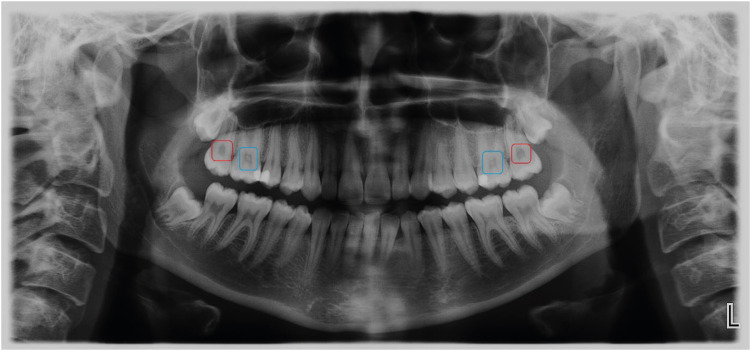

The panoramic images requested for dental diagnostic purposes were obtained by using the Planmeca ProOne Digital Panoramic X-Ray Machine with 60–70 kVp, 2–7 mA and 2–10 seconds exposure time (Planmeca Group, Helsinki, Finland). The radiographic images were evaluated under standard radiological examination conditions according to the presence or absence of pulp stones (Figure 2). On the panoramic images, the patients having a pulp stone in at least 1 tooth were recorded as the “pulp stone group” while patients who had no pulp stone in any teeth were the “control group”. Considering that the presence of pulp stones within the pulps of the extracted teeth may influence the findings of the present study, the patients with tooth loss (except third molars) were excluded from the study.

Figure 2

Blue and red boxes on the panoramic image show teeth with or without pulp stone, respectively.